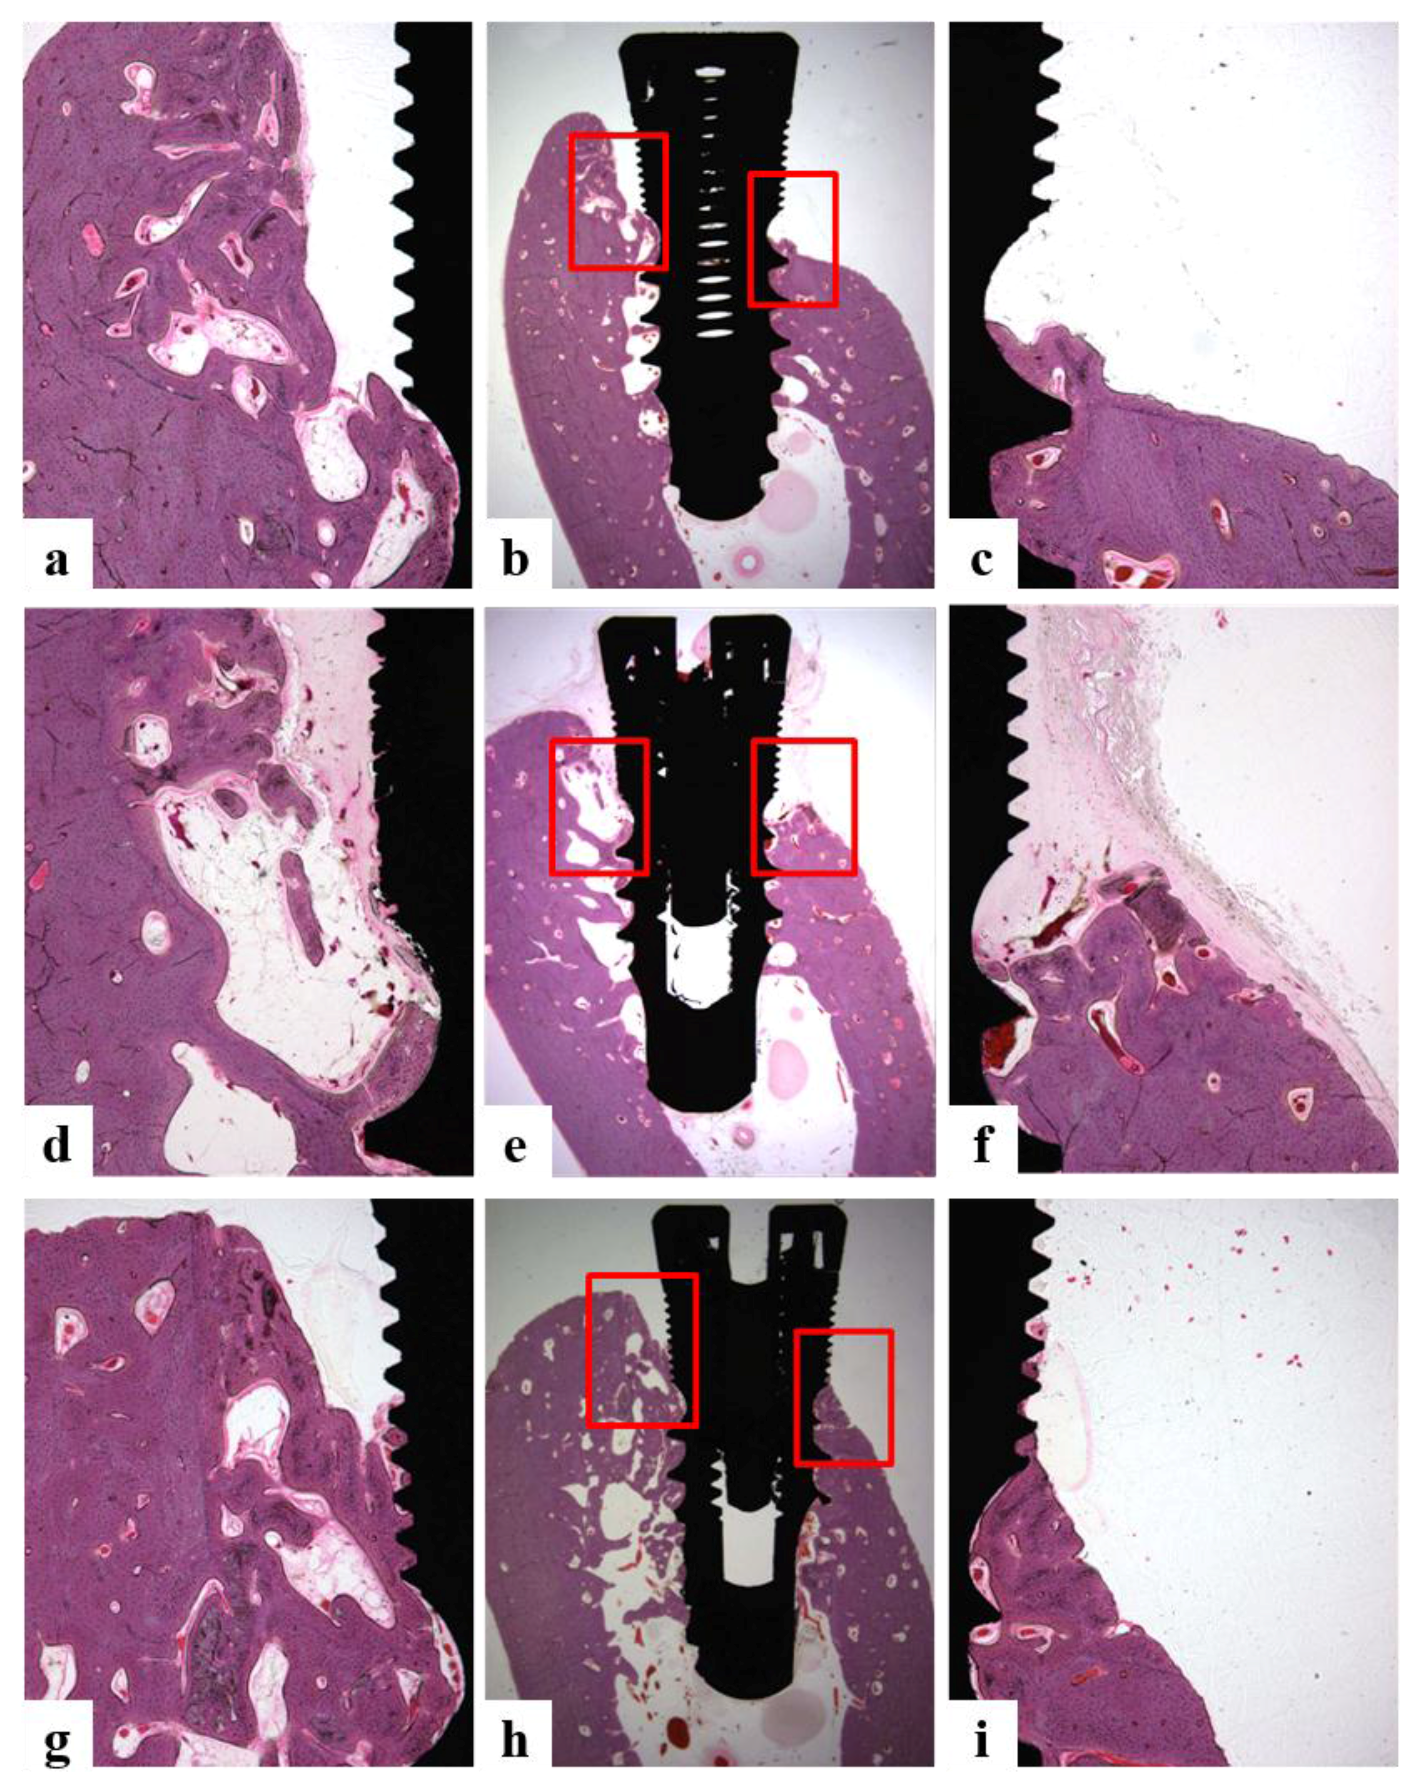

2.5.6. Histologic and Histometric Analysis

- Bone growth height in buccal defect areas (BG, mm): The thickness of bone that grew upward from the implant from the reference point on the buccal defect site on the alveolar ridge.

- Bone to implant contact in microthreads (microBIC, %): The bone to implant contact ratio was measured in buccal and lingual defect areas where the bone grew along the implant from the implantation reference point on the alveolar ridge.

- Bone to implant contact in macrothreads (macroBIC, %): The bone to implant contact ratio was measured in existing bone where the implant was implanted.

- Intra-thread bone density in macrothreads (ITBD, %): Intra-thread bone density was measured in the existing bone where the implant was placed.

3.4.4. Histomorphometric Analysis

| Group | BG (mm) | microBIC (%) | macroBIC (%) | ITBD (%) |

|---|---|---|---|---|

| Ti | 0.23 ± 0.22 a | 11.05 ± 5.09 a | 23.58 ± 1.63 a | 54.90 ± 7.24 a |

| Hepa/Ti | −0.06 ± 0.21 a | 9.27 ± 1.95 a | 18.47 ± 2.89 a | 53.98 ± 3.77 a |

| PDGF/Hepa/Ti | 0.12 ± 0.28 a | 9.59 ± 3.99 a | 20.62 ± 2.30 a | 61.64 ± 6.17 a |

| BMP/Hepa/Ti | 1.34 ± 0.17 b | 27.76 ± 3.03 b | 22.20 ± 2.89 a | 60.80 ± 3.32 a |

| PDGF/BMP/Hepa/Ti | 1.31 ± 0.12 b | 31.79 ± 3.90 b | 23.54 ± 2.30 a | 69.22 ± 3.96 a |

| * p | 0.000 | 0.000 | 0.544 | 0.244 |